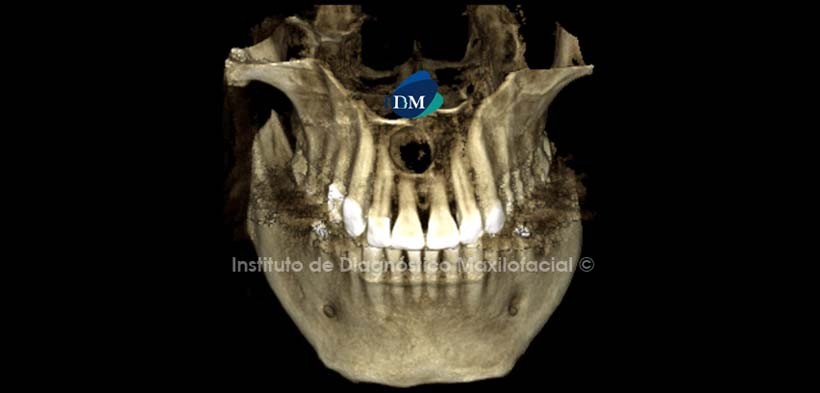

A la evaluación de la radiografía panorámica se observa pieza 36 con corona metal- cerámica, pilar de puente protésico, obturación de conductos y espigo muñón, evidenciándose un proceso osteolítico periapical. Se observa además una imagen radiolúcida de forma redondeada de límites definidos, bordes corticalizados proyectada sobre la línea media maxilar que se extiende desde ápice de pieza 1.2 hasta ápice de pieza 2.2; y desde tercio apical de piezas 1.1, 2.1 hasta proximidades de piso de fosas nasales. (Figura 1)

A la evaluación de la tomografía volumétrica (CBCT) en cortes axiales realizados a diferentes niveles, observamos la dilatación del conducto naso palatino como se muestra en el corte a nivel de la espina nasal anterior (figura 2), y en el corte a nivel apical de piezas antero superiores (Figura 3).